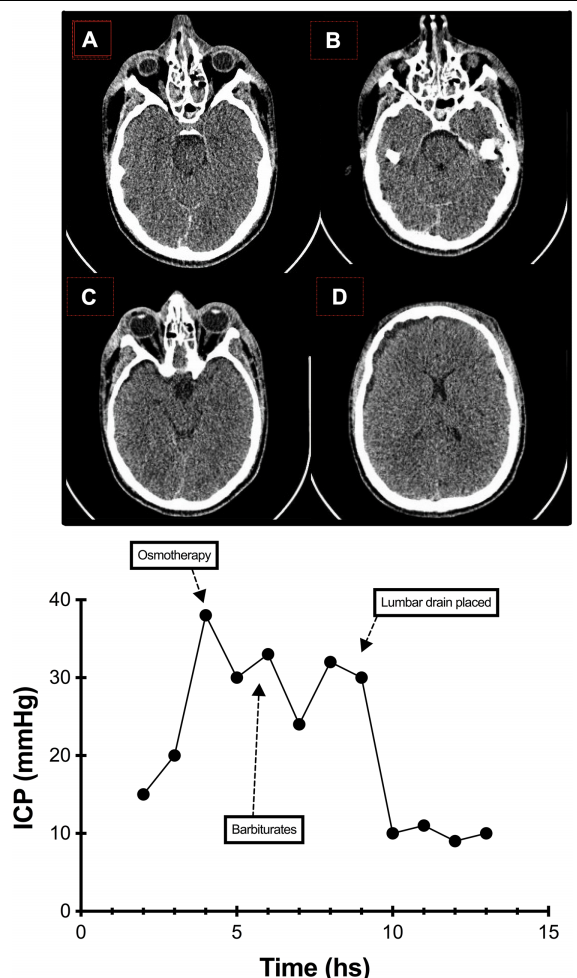

• • 一名50岁的女性患者突发头痛、呕吐和昏迷。头部CT扫描显示在外侧裂中存在较大血块,未及脑室出血或梗阻性脑积水。CTA提示一侧大脑中动脉瘤,在12小时内进行了夹闭手术,并植入了硬脑膜下导管监测颅内压。患者在使用镇静、高渗盐渗透治疗、神经肌肉阻滞剂和巴比妥类药物后仍存在颅内高压。神经外科进行了去骨瓣减压术,术后的头颅CT如图2所示。尽管进行了手术,患者颅内压仍高(在30-35mm Hg之间),因此置入了腰大池引流管(见图3),颅内压立即控制在15mm Hg以下水平,并减轻了其他治疗措施的需求。患者在6个月时的GOSE评分为7,预后良好。

腰穿有什么用病例系列报道——使用控制性腰穿引流治疗基底池未闭的难治性颅内高压_https://www.jmylbn.com_新闻资讯_第3张

图2 案例3。头颅CT示动脉瘤夹闭后和去骨瓣减压术后改变,同时可见蛛网膜下腔出血及外侧裂较大血块,中线无移位,基底池未闭。

腰穿有什么用病例系列报道——使用控制性腰穿引流治疗基底池未闭的难治性颅内高压_https://www.jmylbn.com_新闻资讯_第4张

图3 案例3。该图显示了平均颅内压(ICP)及其对治疗干预的反应(如图所示)。它清楚地表明,对一级治疗(渗透治疗)和二级治疗(巴比妥类药物和去骨瓣减压术)均未下降至正常范围内。置入腰大池引流管后颅内压立即得到控制。该图显示平均每小时的ICP。